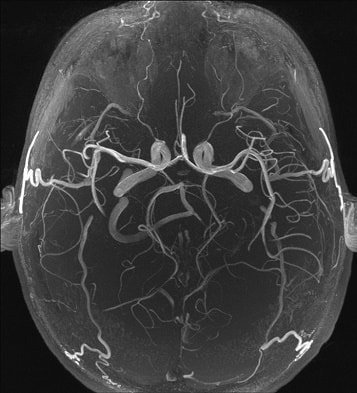

- МР-ангиография предусматривает осуществление обследования способом магнитно-резонансной томографии чаще без предварительного контрастирования.

MРA означает магнитно-резонансная ангиография. Мра сосудов головного мозга проводится для оценки нарушений в системе притока артериальной крови к головному мозгу.

Трехмерная (3D) времяпролетная ангиография time-of-flight (TOF) МRА является наиболее распространенным методом, используемым для оценки системы артериального кровоснабжения головного мозга.

МРА 3D TOF обеспечивает более высокий сигнал-шум (signal-to-noise) и короткое время обработки изображений. MРA головного мозга проста в выполнении и не требует контрастного усиления.

МР-ангиография сосудов головного мозга и других вен выполняется с применением контрастных веществ или без них. На снимках видны не только патологические отклонения некоторых сосудов, но и их выраженность. Нередко для получения полной картины заболевания проводится МРТ головного мозга с ангиографией.

Магнитно-резонансная ангиография (МРА) широко применяется в исследованиях магистральных артерий в экстра- и интракраниальном отделах. МРА достаточно информативна для визуализации сонных, позвоночных и внутримозговых артерий.

Она дает возможность, не применяя контрастного усиления, без риска для пациента визуализировать большинство сосудистых поражений головного мозга и магистральных сосудов головы в экстракраниальном отделе.

На МР-ангиограммах сосуды визуализируются как трубчатые структуры с повышенной интенсивностью сигнала на фоне низкоинтенсивных прилегающих тканей. Сигнал от кровотока в них однородный, определяется четкостью контуров артерий, вен и венозных пазух.

MP-ангиография, проведенная на уровне артериального круга мозга, позволяет визуализировать внутренние сонные и средние мозговые артерии, проксимальные отделы передних мозговых артерий, основную и задние мозговые артерии. Передние и задние соединительные артерии, а также дистальные отделы мозговых артерий не определяются из-за малого их диаметра.

Исследование проводится безболезненно. МР-ангиография сосудов головного мозга дает очень точную диагностику, в результате исследования выдается трехмерное изображение, проводится проверка состояния сосудов и капилляров.